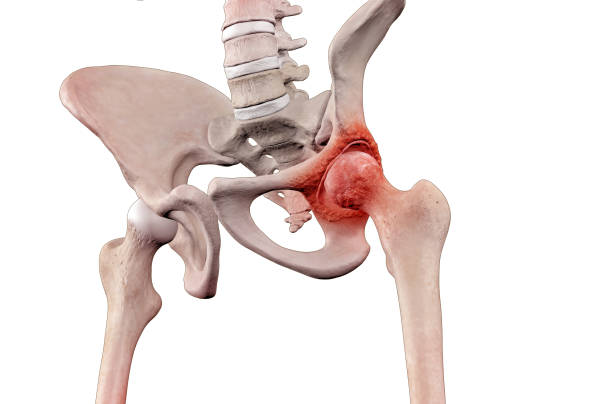

요추 전만은 허리디스크 치료와 예방에서 핵심적인 역할을 합니다. 요추 전만을 만들면 디스크의 압력이 감소하고 허리디스크 증상을 완화할 수 있습니다. 이를 위한 두 가지 자세가 있습니다.

오리 궁둥이 방법은 골반을 앞으로 돌리면서 엉덩이를 뒤로 빼는 자세입니다. 이 자세를 취하면 요추 전만 곡선을 만들게 됩니다.

하지만 주의할 점은 오리 궁둥이 방법은 디스크 손상을 쉽게 일으킬 수 있으므로, 이 자세를 유지하려면 등 뒤에 있는 근육을 강하게 수축시켜야 합니다. 이로 인해 디스크 내부의 압력이 높아져 디스크가 더 찢어질 수 있습니다.

당당한 가슴 방법은 골반을 그대로 고정하고 척추의 뒷부분만을 뒤로 젖혀 요추 전만 각도를 만드는 자세입니다. 이 자세는 상체 무게가 허리 뒤로 떨어지게 되어 디스크에 압력을 덜 가하게 합니다.

디스크 압력이 낮아지므로 허리디스크 증상을 완화하는데 도움이 됩니다.